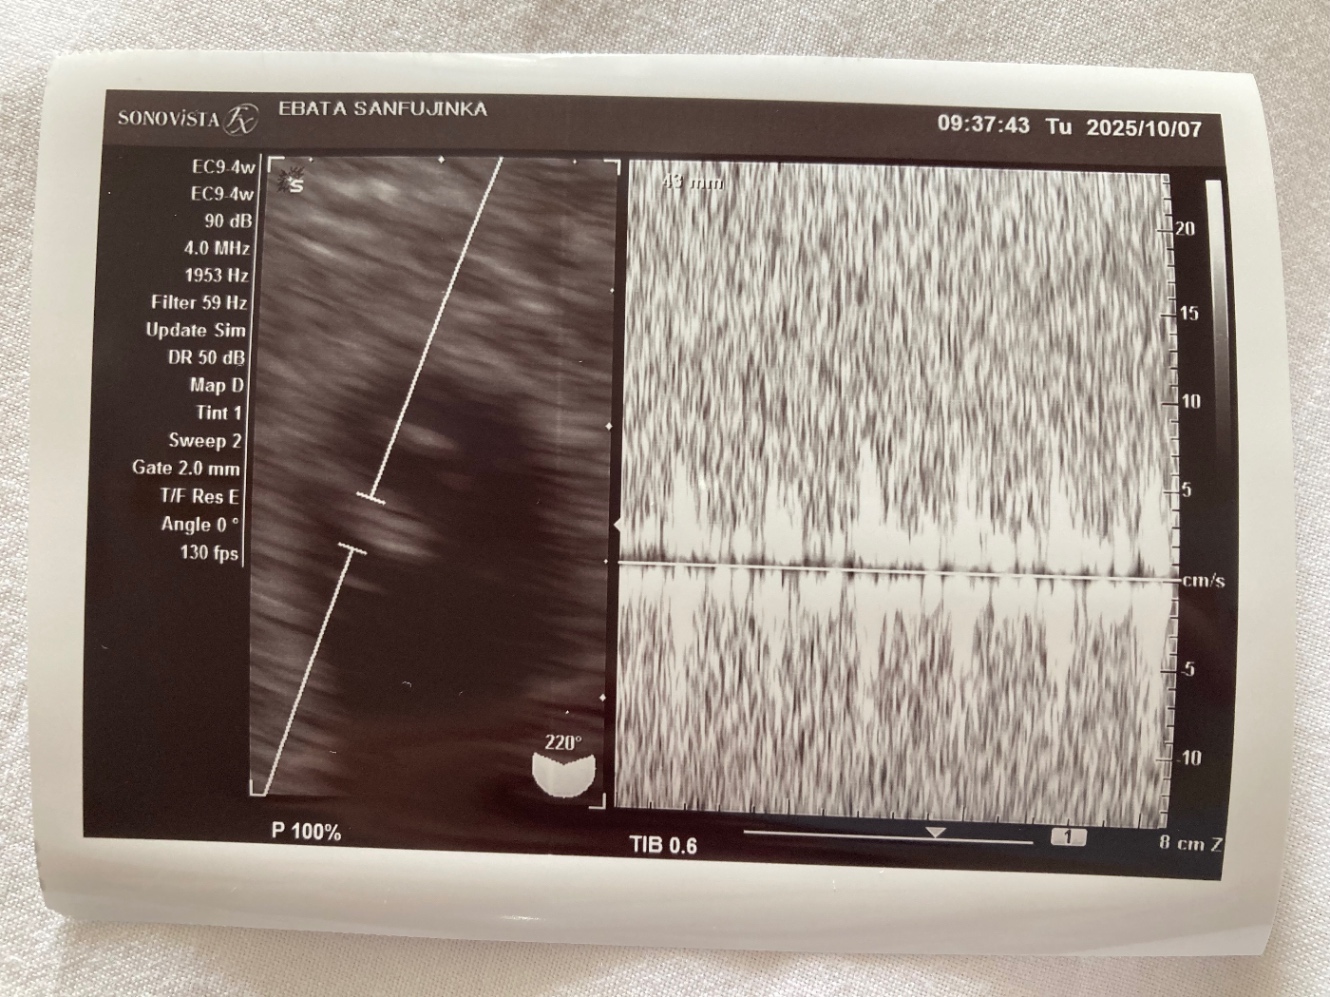

「まだ茶おりありますね」たくさんの患者さんが待っていたがすぐに診察が始まった。『茶おり』とは『茶色いおりもの』のことだ。続いてエコー。

「動いていますよ。心臓」

「音聞きましょう」

ドクッドクッドクッドクッ

早い脈拍が聞こえた。

左が赤ちゃんの影。右が心拍のリズム。